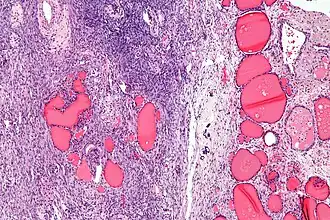

| Lâmina histológica de um struma ovarii. Pode-se observar folículos tireoideanos na direita, e estroma ovariano na esquerda. | |

Struma ovarii é um tumor do ovário, geralmente benigno e unilateral. Ele é uma variante de teratoma maduro, composta por mais de 50% de tecido tireoideano maduro. Corresponde a cerca de 1% de todos tumores de ovário e 2,7% dos teratomas maduros.[1]